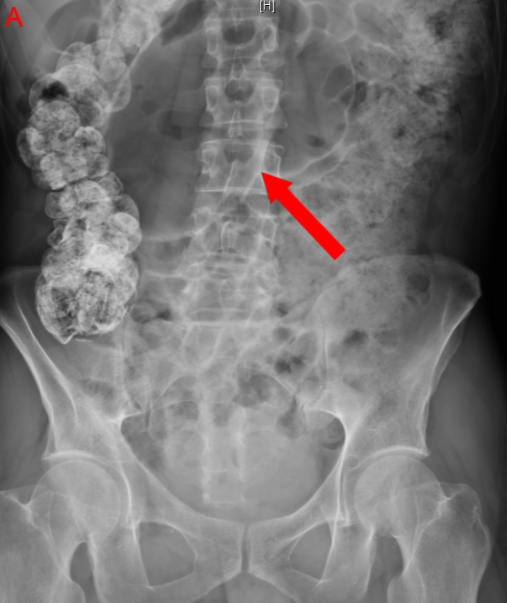

Q

What is the abnormality

A

colonic volvulus. See dilated sigmoid colon (whirl pattern) around mesocolon and vessels creating a bird beak appearance.

Can see it better with barium enema with water solbule contrast if uncertain diagnosis.

volvulus and twisting of gut and cause torsion and gangrene

See distended proximal large bowel and airfluid levels in the small intestine.